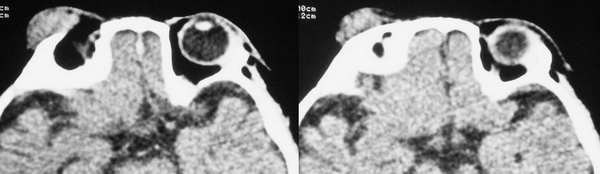

4m发现右眼周外上象限肿物年余 渐增大 软无波动

片不是很清晰,病变位置在外上象限,外直肌中远部增粗,但主要是向外膨胀,边光整,骨质无殊,与颅内无明显相关,以右侧泪腺区占位,混合瘤可能,做增强吧.

泪腺的肿瘤我认为完全可以排除,因为右侧泪腺显示的很好,肿瘤位置较为表浅,位于皮下,和泪腺无明显关系。该肿瘤为来源于软组织的肿瘤,软组织肿瘤种类繁多,影象学的目的更主要的是观察病变的范围和其与临近结构的关系,估计良恶性。该肿瘤边界清楚,与皮肤无粘连,无骨质侵蚀,考虑为良性,以血管瘤和神经纤维瘤的可能性略大些。

首先考虑眼眶毛细胞血管瘤。

横纹肌肉瘤多伴有骨质破坏,本例也应考虑无骨质破坏的横纹肌肉瘤。